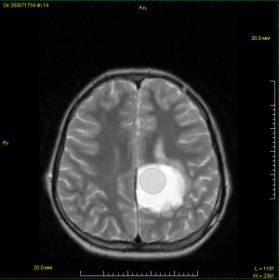

У 38 больных первично

эхинококкоз головного мозга

диагностирован по особенностям

динамики клинического течения

заболевания с применением компьютерной и ядерно-магнитной резонансной

томограммы. (рис 1.)

Рис.

1. На ЯМРТ визуализируется однокамерная эхинококковая киста темено-височной

области головного мозга